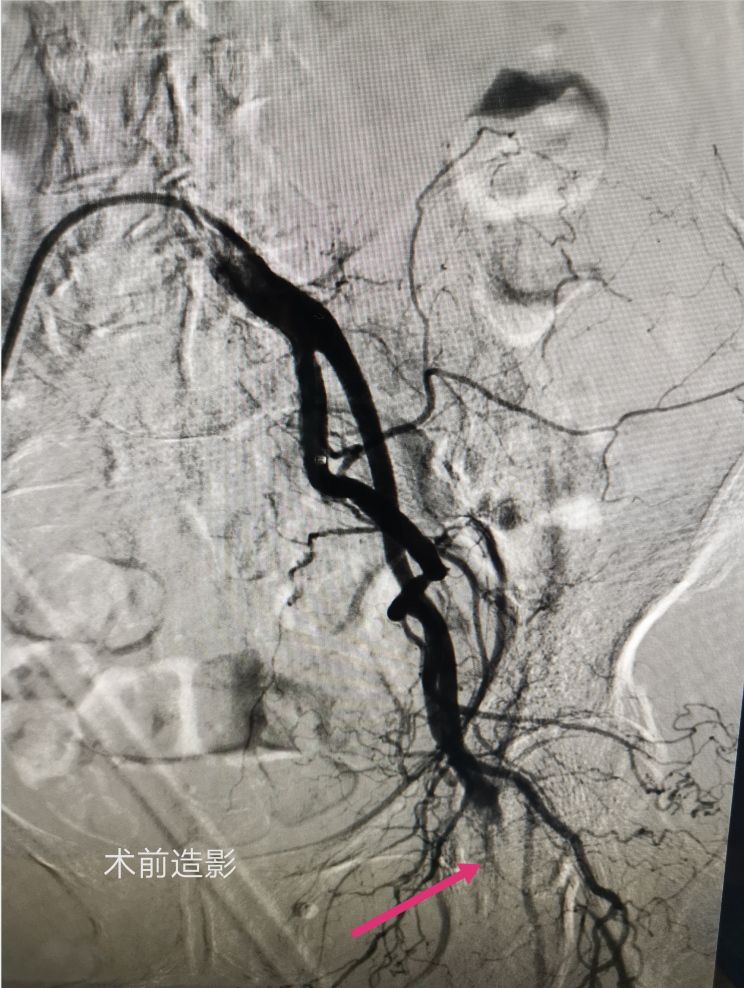

经右侧股动脉穿刺造影见股总动脉、股深动脉、股浅动脉闭塞。

远端造影见腘动脉闭塞